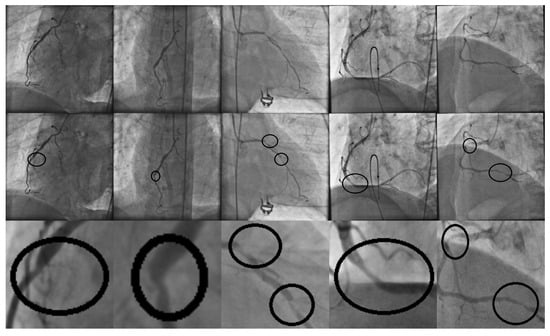

In order to evaluate the obtained results, a dataset was formed from the second image database described in Section 2.1. The dataset was divided into the training set with ≈65% (1828 instances) and testing set (960 instances). In Figure 6, sample patches corresponding to the second dataset, are presented.

Figure 6.

Patch samples from the second database of 2788 images. Rows (1) and (2) correspond to positive stenosis cases. Rows (3) and (4) correspond to negative stenosis cases. Column (a) corresponds to the original patch image. Columns (b–i) correspond to the different enhancement method responses as follows: Frangi, Salem, simple-scale Gabor, multi-scale Gabor, multi-scale linear, multi-scale matched filter, single-scale matched filter, and top-hat operator.